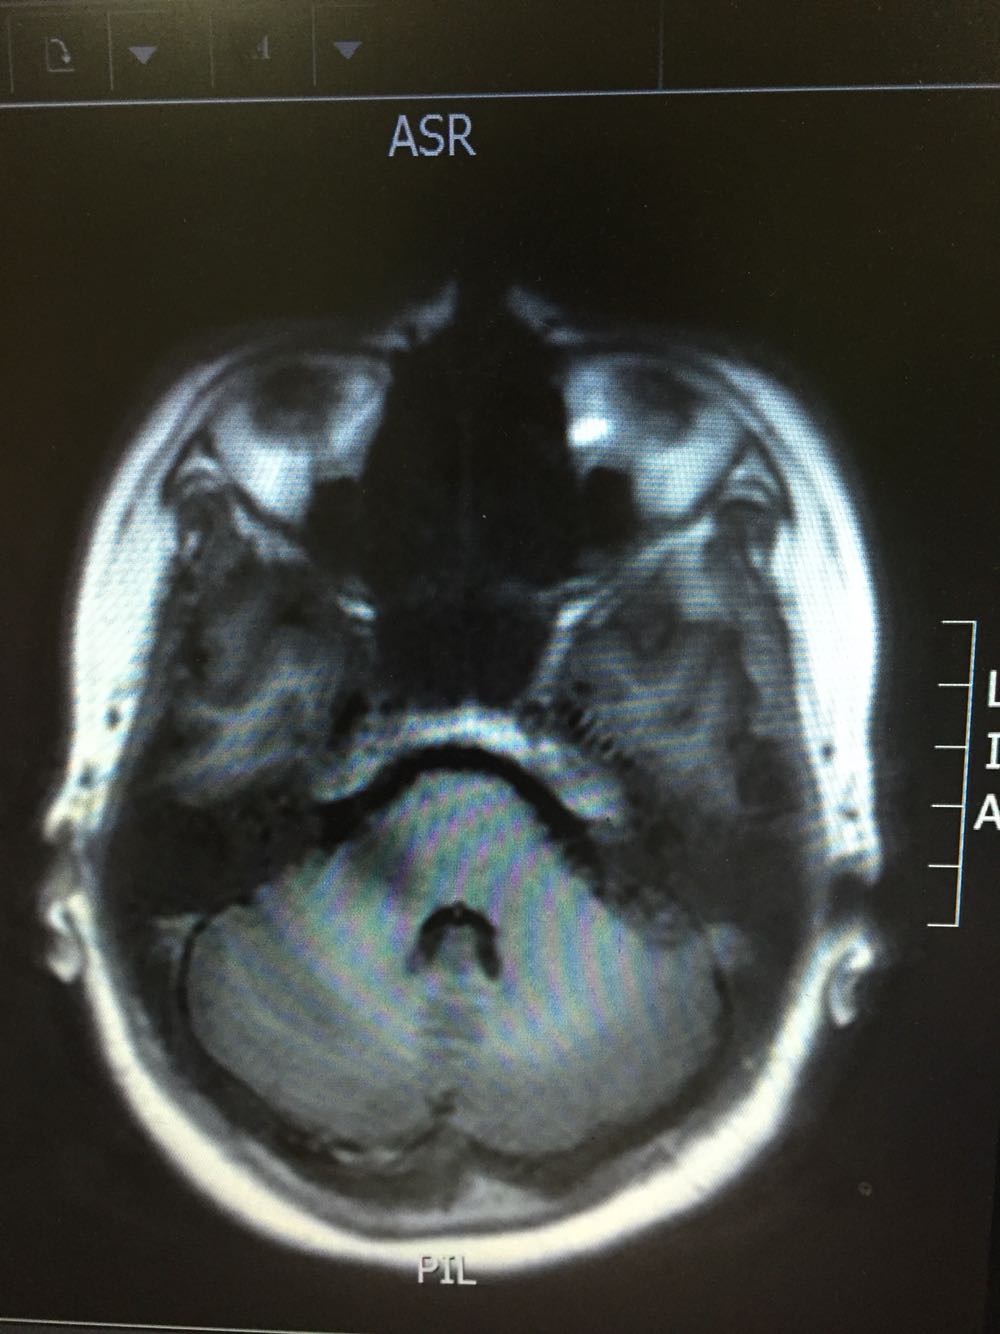

女,35岁,因“右侧肢体无力伴语笨9日”由门诊收入病房。病例特点:1.既往史:青年女患,既往否认高血压病史,否认糖尿病及冠心病史,否认药物、食物过敏史。2.现病史:该患者于入院前9日始出现右侧肢体无力,伴语笨,伴有恶心、呕吐,不伴有头痛,偶有头晕,不伴有尿便障碍,不伴有抽搐发作,为求进一步诊治而来我院。

查体:体温:36。5℃,脉搏:70次/分,呼吸:18次/分,血压:121/79mmHg,神志清楚,言语流利,查体合作,双侧瞳孔等大同圆,对光反射存在,双眼活动自如,鼻唇沟对称,伸舌居中,右侧肢体肌力4级,肌张力正常,腱反射对称,双侧感觉对称,右下肢Babinski征(+)、Chaddock征(+)、颈强(-),克氏征(-)。 脑脊液免疫球蛋白A0.003g/L 抗酸杆菌、墨汁染色阴性,余脑脊液化验未见异常。脑脊液外观无色透明

桥脑脱髓鞘病变可能性大甲强龙冲击治疗

初始考虑青年脑梗死待磁共振增强回报后考虑能否占位可能脑功能成像及脑脊液结果回报后考虑桥脑脱髓鞘病变可能性大,给予甲强龙冲击治疗,冲击治疗后患者症状逐渐好转,右侧肢体肌力出院时5-级。